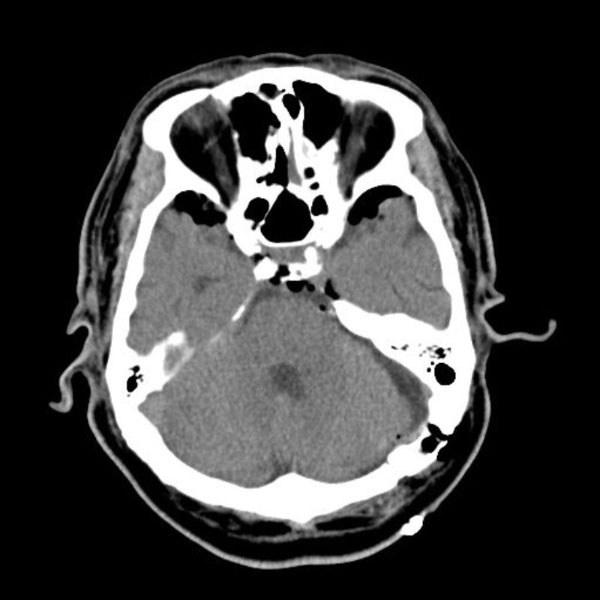

手術前

(MR1)

(CT)